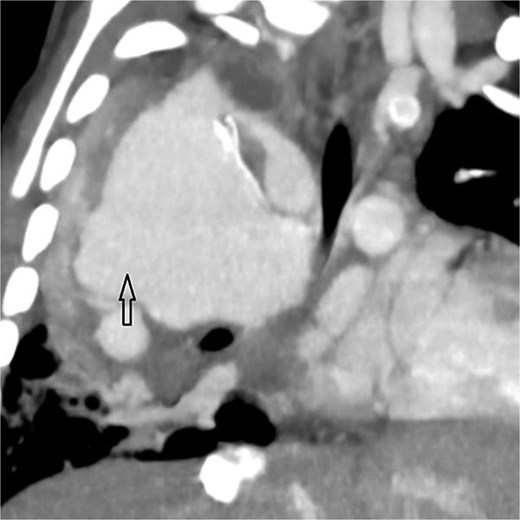

Axial CT angiogram in lung window demonstrating right lower-lobe consolidation and volume loss with mediastinal shift, consistent with pneumonia and compression by the pseudoaneurysm.

Urgent transthoracic echocardiography demonstrated a large echodense mass in the right hemithorax, compression of the right atrium and reduced flow through the right-sided shunt. Computed tomography angiography (CTA) confirmed a massive saccular pseudoaneurysm (≈8 × 7 × 6 cm) arising from the anastomosis between the right subclavian artery and the mBTTS graft, completely thrombosed without active contrast extravasation (Fig. 1). There was complete thrombotic occlusion of the right pulmonary artery, right lung collapse due to extrinsic compression and right lower-lobe consolidation consistent with pneumonia (Fig. 2). CTA also revealed left isomerism with central liver and polysplenism (Fig. 3) and a horseshoe kidney (Fig. 4), suggesting a previously unrecognized polymalformative syndrome.